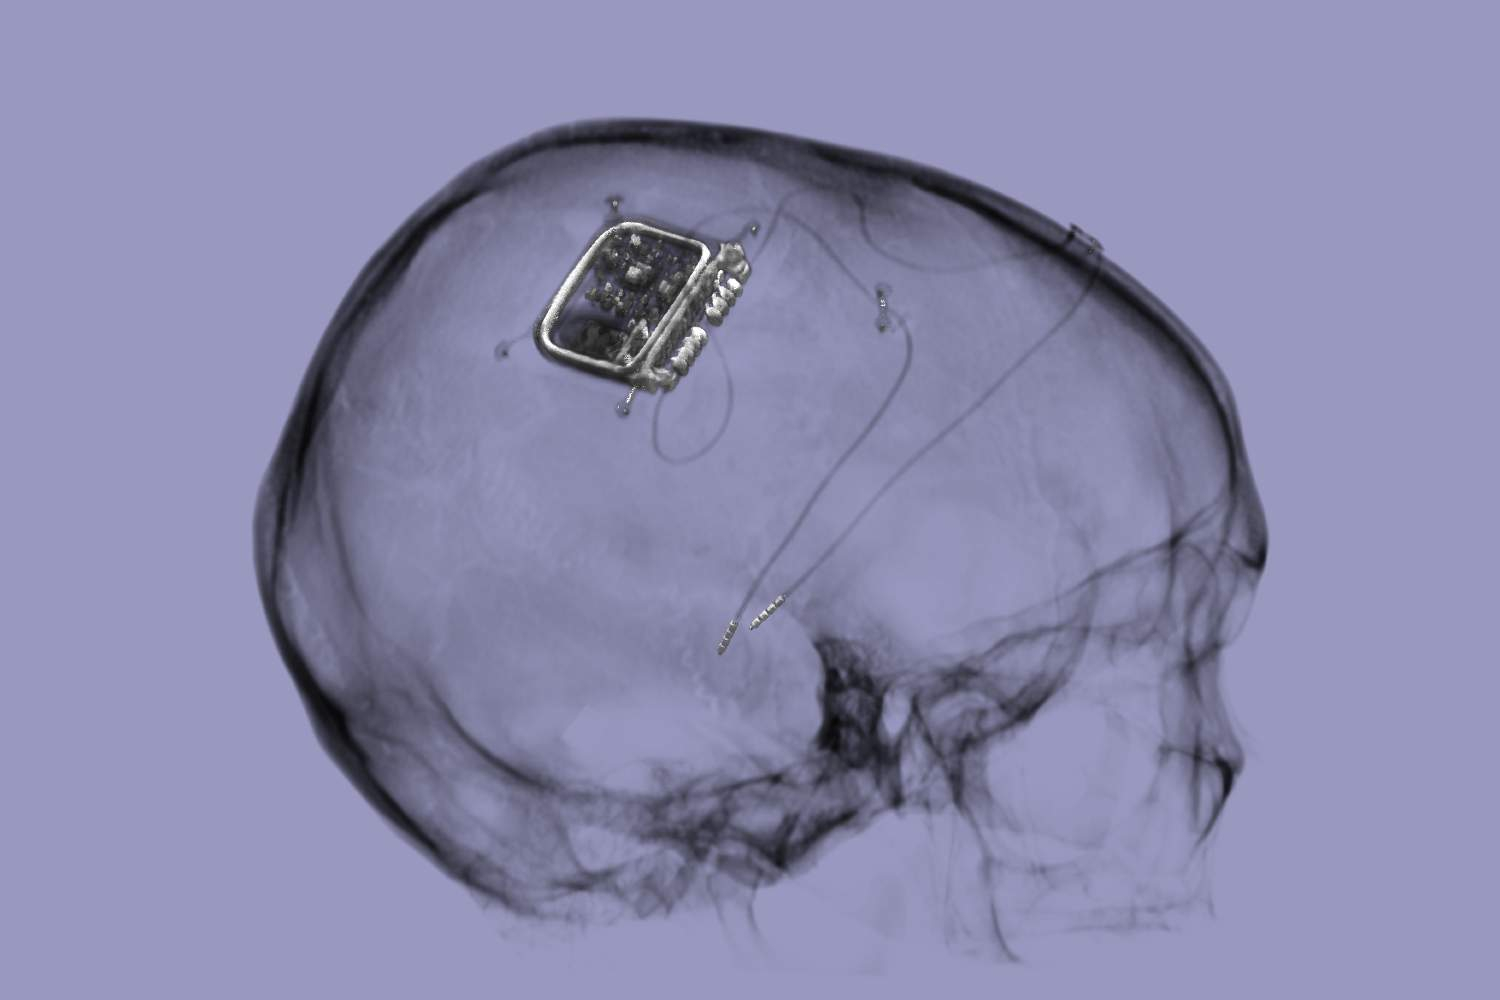

Harnessing neural dynamics to transform device-based therapy for brain disorders